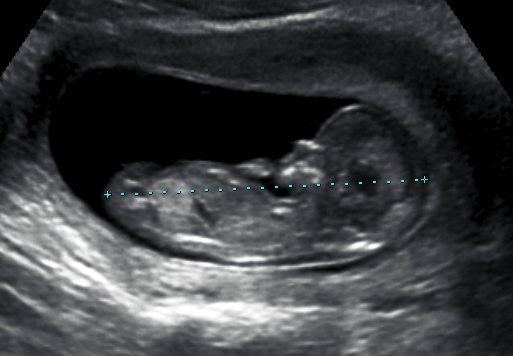

I think blue too. Some stacking happening on that nub!

Really? I think the nub is straight with the spine line. I'll be the odd one out and say girl.

Me too, I think girl...